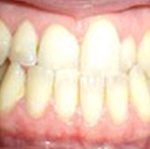

Avant traitement

Après traitement